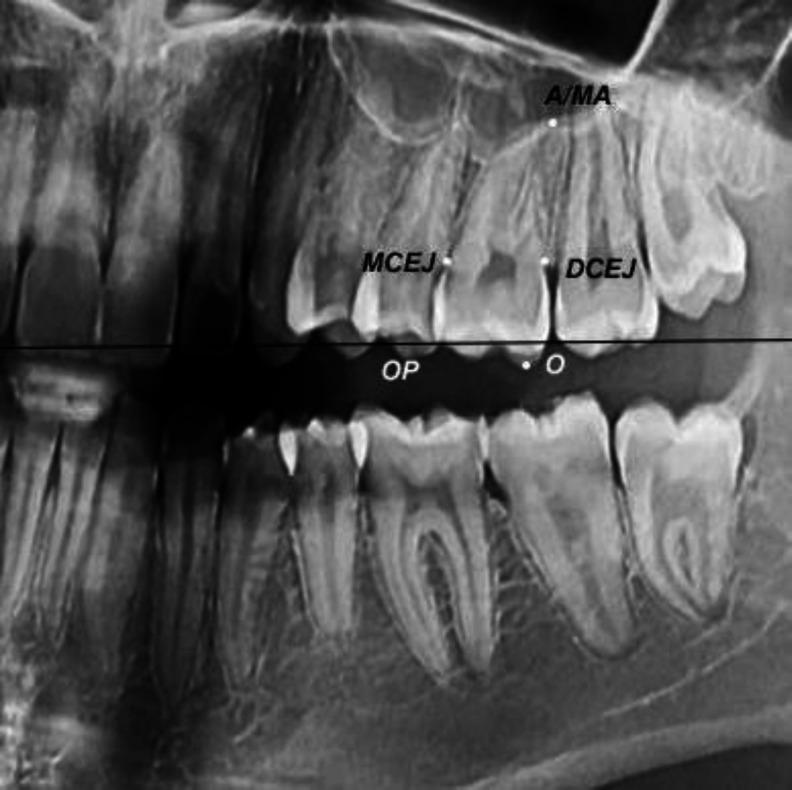

This study assessed sex estimation of Iranians according to maxillary left first molar measurements made on panoramic radiographs using classical and machine-learning classifiers. In this cross-sectional study, tooth length- and width-related variables were calculated for maxillary left first molars on 131 panoramic radiographs (65 males, 66 females; age range of 18-30 years). A subsample of the radiographs was selected and reevaluated by two examiners after 1 month. The intra-class correlation coefficient (ICC) was calculated to assess reliability. The regularized discriminant analysis (RDA), support vector machine (SVM), and cascade-forward and feed-forward neural network models were used for sex estimation. Comparisons were made with the Mann-Whitney and t tests. The intra-observer reliability was 0.9. SVM had the best performance on the test data in both classification schemes. The crown length at the cementoenamel junction (CEJL) and total crown length (CL) in the classification scheme I (sex estimation based on length and width variables), and CEJL/root length (RL), cementoenamel junction width (CEJW)/CEJL, and RL/total tooth length (TTL) in the classification scheme II (sex estimation based on the ratio of variables) were important variables for sex estimation determined by the SVM model. The CEJL had the highest discriminative potential with an area under the curve (AUC) of 78.8. The ratio of variables did not substantially improve sex estimation compared with single variables. CEJL is a reliable measure for sex estimation in Iranians with values higher than 6.25 indicating the male sex and other values indicating the female sex.

本研究根据在全景X光片上对上颌左侧第一磨牙进行的测量,使用经典分类器和机器学习分类器评估伊朗人的性别估计。在这项横断面研究中,计算了131张全景X光片(65名男性,66名女性;年龄范围为18至30岁)上的上颌左侧第一磨牙与牙长和牙宽相关的变量。选取了一部分X光片样本,1个月后由两名检查人员重新评估。计算组内相关系数(ICC)以评估可靠性。使用正则判别分析(RDA)、支持向量机(SVM)以及级联前馈和前馈神经网络模型进行性别估计。采用曼-惠特尼检验和t检验进行比较。观察者内可靠性为0.9。在两种分类方案中,SVM在测试数据上的表现最佳。在分类方案I(基于长度和宽度变量的性别估计)中,釉牙骨质界处的冠长(CEJL)和总冠长(CL),以及在分类方案II(基于变量比率的性别估计)中,CEJL/根长(RL)、釉牙骨质界宽度(CEJW)/CEJL和RL/总牙长(TTL)是SVM模型确定的性别估计的重要变量。CEJL具有最高的判别潜力,曲线下面积(AUC)为78.8。与单一变量相比,变量比率并未显著改善性别估计。CEJL是伊朗人性别估计的可靠指标,值高于6.25表明为男性,其他值表明为女性。